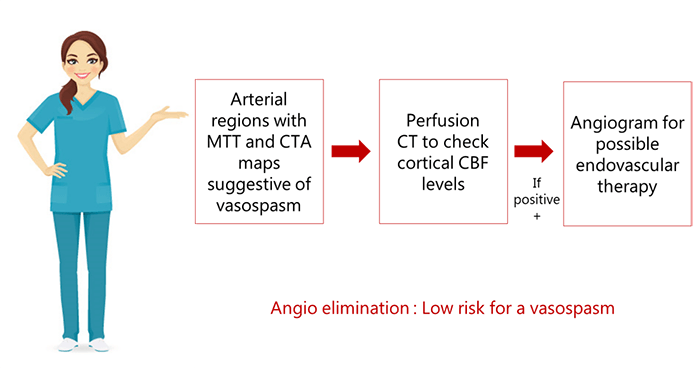

A better approach is to combine perfusion CT with CT angiography to monitor hemodynamics in patients with SAH. On perfusion CT, any arterial territory with prolonged MTT is known to be a potential site for vasospasm.

In cases where arterial regions produce MTT and CTA maps suggestive of vasospasm, cortical CBF levels can be checked via perfusion CT. Patients who are positive can be followed with an angiogram for possible endovascular therapy. This approach is more sensitive and specific than Doppler alone, and presents the advantage of eliminating the need for invasive angiograms.